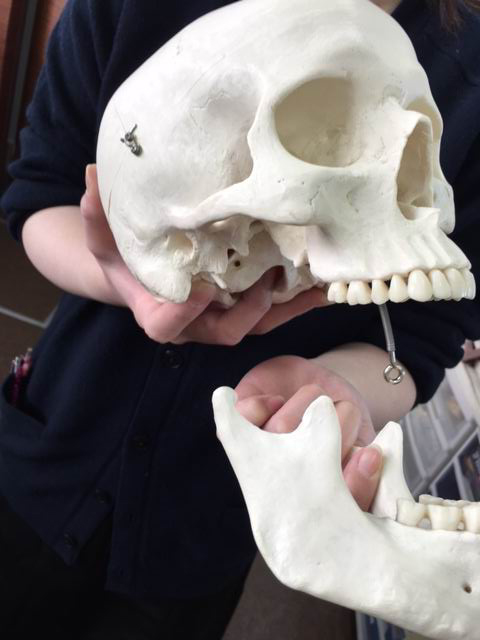

※これはある患者さんの骨の模型です。右上に穴が空いている部分があります。

頭蓋骨をご覧頂くともっとよくわかりますね。

鼻とお口はこうして

繋がっているんです。

※これはある患者さんの骨の模型です。右上に穴が空いている部分があります。